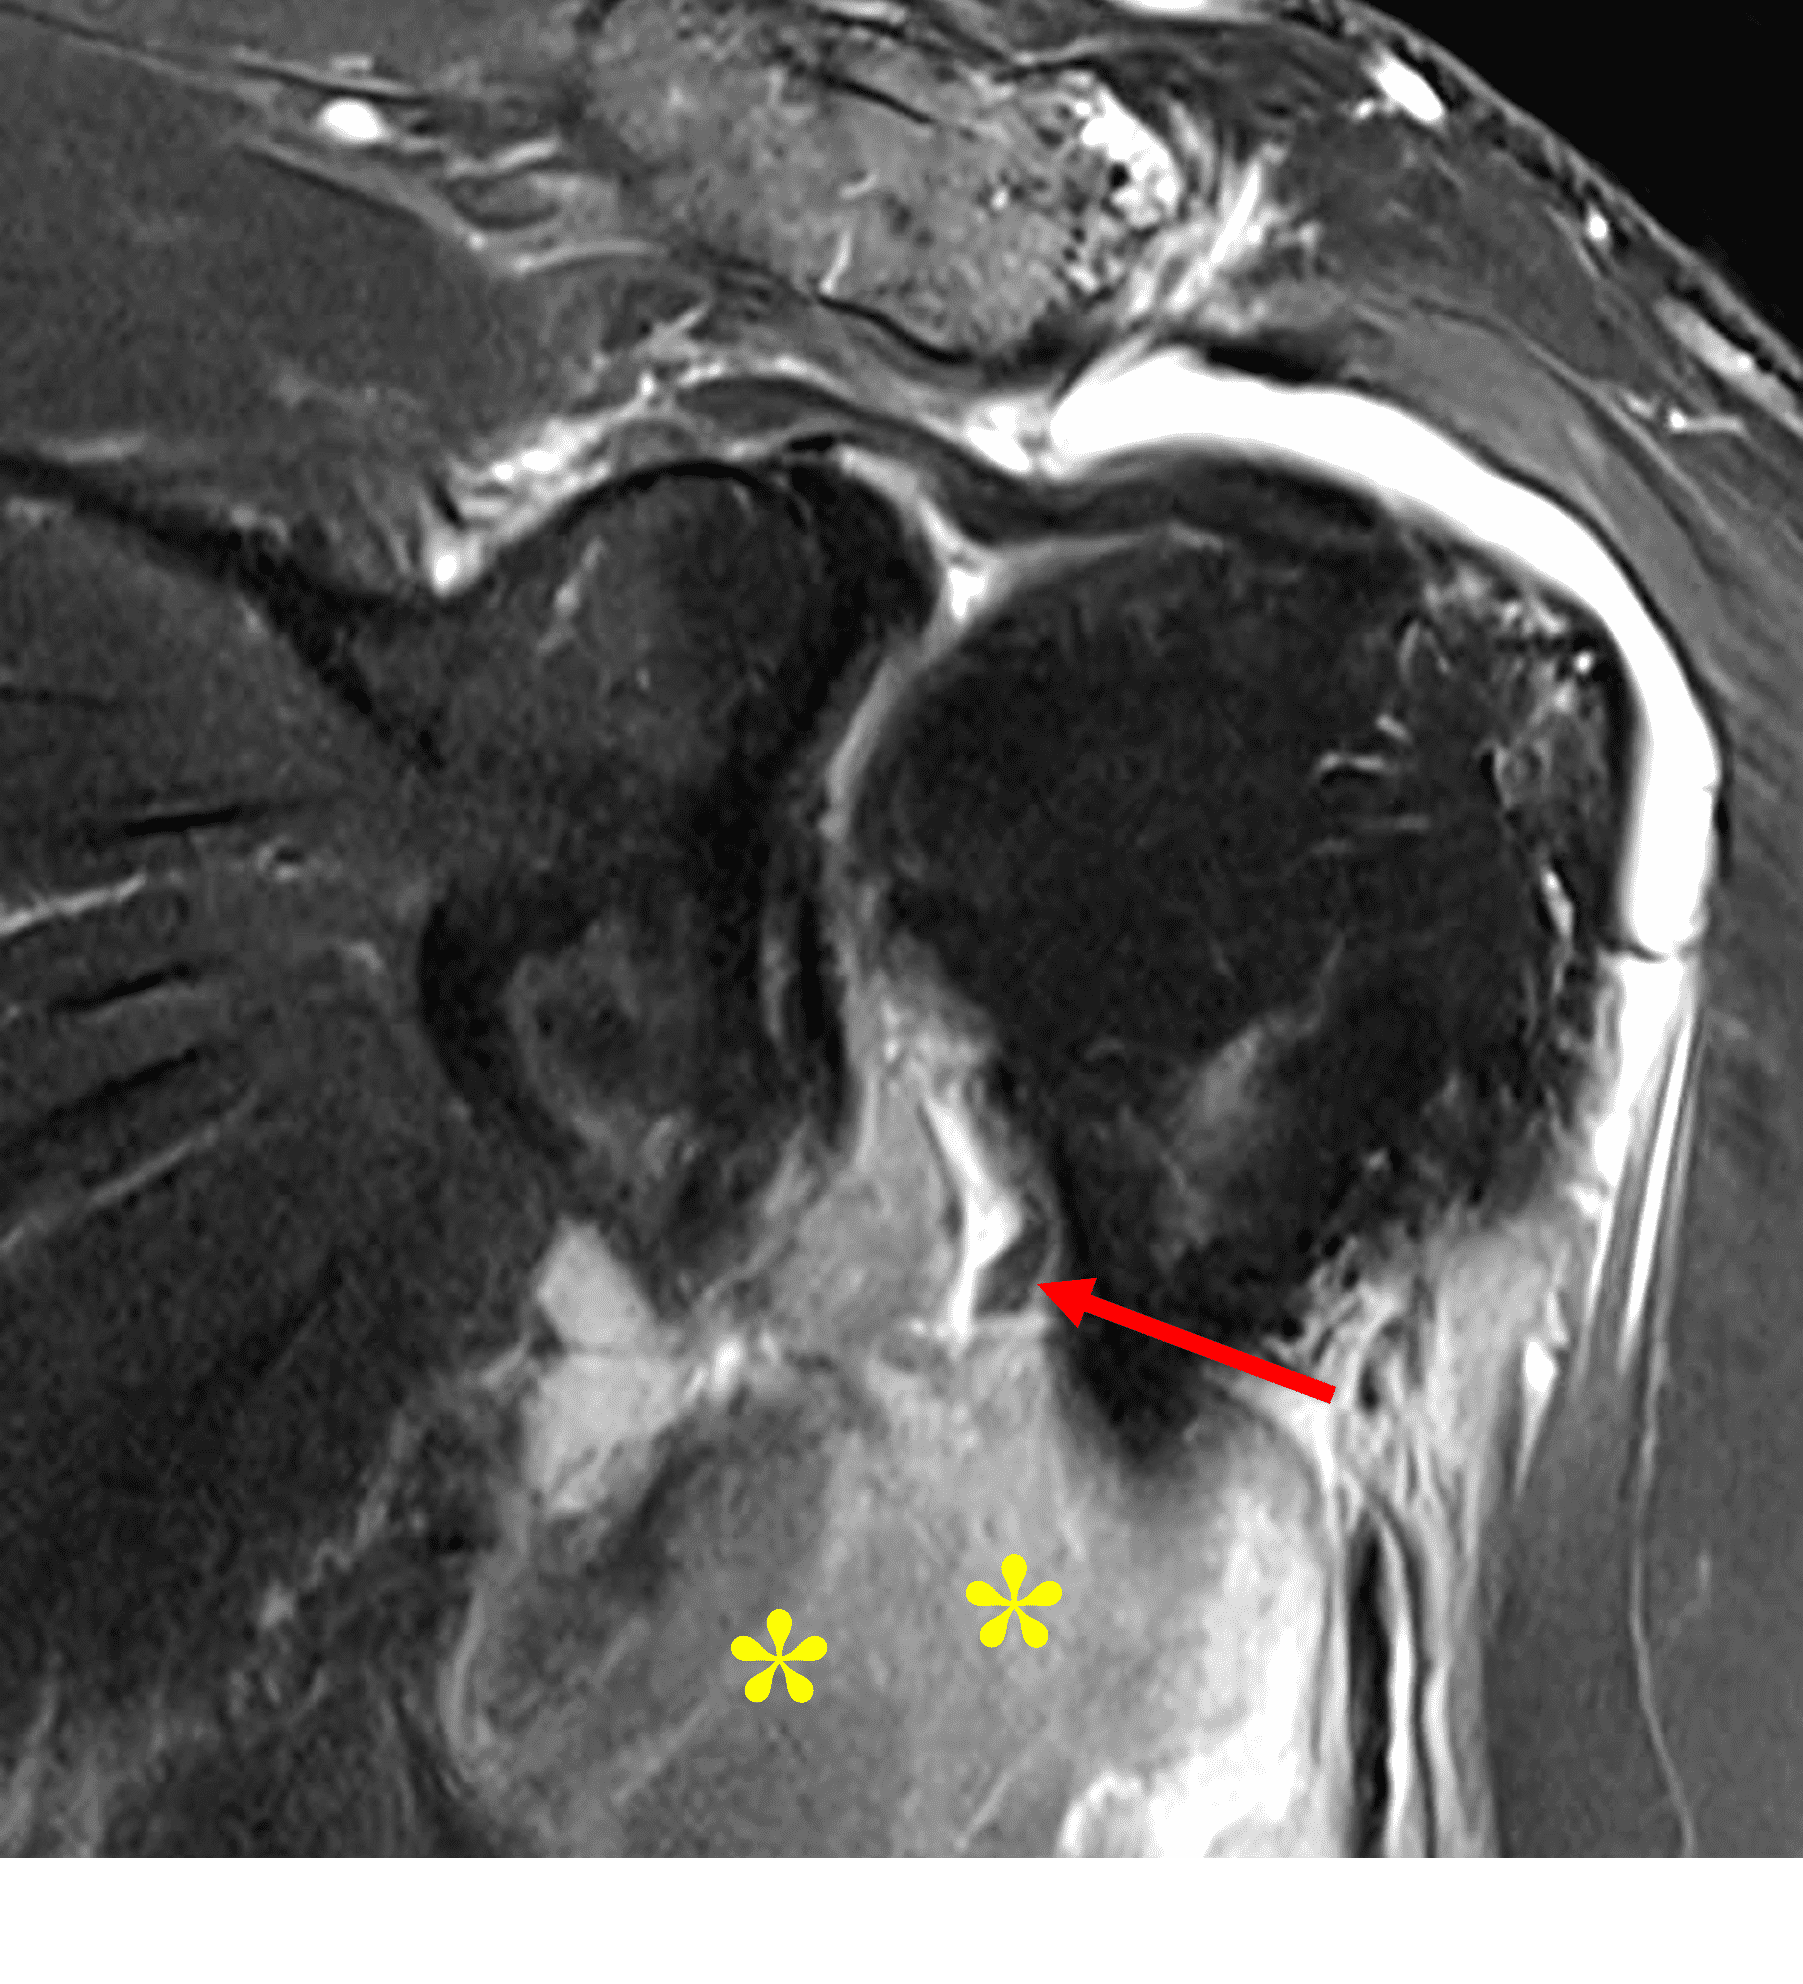

Figure 2: (2A) An axial image at the level of the humeral lesser tuberosity (LT) shows an intact subscapularis tendon (arrowheads). (2B) More inferiorly at the level of the humeral neck (HN), the direct muscular attachment of subscapularis (yellow arrows) is avulsed from the humerus together with the anterior band of the inferior glenohumeral ligament (red arrow), representing humeral avulsion of the glenohumeral ligament, a HAGL lesion. (2C) A coronal image through the anterior humerus shows the avulsed direct muscular attachment of subscapularis (yellow arrows), and the retracted end of the torn anterior band of the inferior glenohumeral ligament (red arrow). (2D) The radiograph shows a small, avulsed bone fragment of the humerus (red arrow), making this injury a “bony” HAGL (BHAGL) lesion. He failed 3 weeks of conservative management, with persistent 7/10 shoulder pain and was managed operatively with a lesser tuberosity repair. 6 months later, after taking a hiatus from baseball, his pain was completely resolved.

Figure 19: Ruptured subscapularis muscle insertion and associated hematoma in a 54-year-old man after a fall. (19A) Coronal fat-suppressed T2-weighted image shows a large hematoma (asterisks) in the area of a ruptured direct attachment of subscapularis to the humeral neck. Also visible is a tear of the anterior band, inferior glenohumeral ligament with small remnant stump (arrow). (19B). Axial fat-suppressed proton-density-weighted image shows the extent of the hematoma (asterisks).